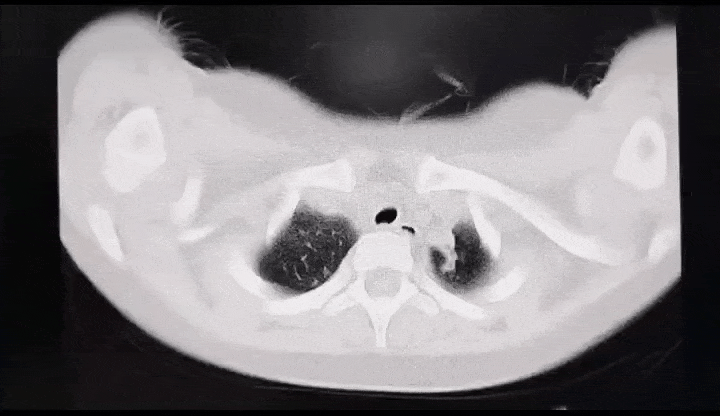

图片

支原体肺炎的影像学表现。图源:深圳卫健委

有的支原体肺炎患儿,肺部影像上显示有一片白色,大多是一个肺叶或一个肺段感染所致,主要是由于气道阻塞物或肺内炎性渗出引起的,但其他的肺叶大多数都是正常的,这和医学上所说的“白肺”是两个概念。

通过拍背排痰、药物祛痰、支气管镜治疗等手段,患儿可以在较短时间内治愈。